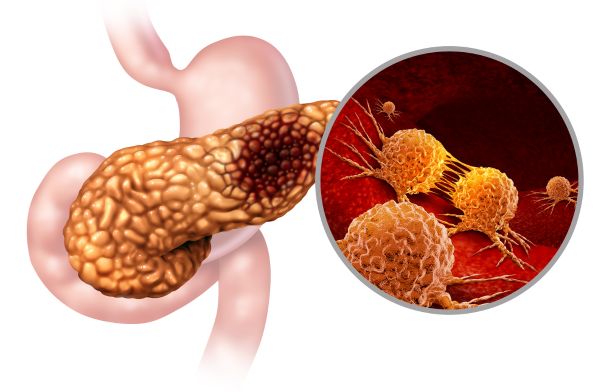

● Trong ung thư học, hình ảnh CT hoặc MRI giúp phân loại giai đoạn (TNM), đánh giá kích thước khối u, di căn hạch hoặc di căn xa.

Các phương pháp chẩn đoán hình ảnh giúp quan sát khối u và đánh giá tính chất

Một trong những giá trị to lớn nhất của chẩn đoán hình ảnh là khả năng tầm soát và phát hiện sớm bệnh lý, ngay cả khi người bệnh chưa xuất hiện triệu chứng. Nhiều chương trình tầm soát hiện nay ứng dụng mạnh mẽ chẩn đoán hình ảnh, điển hình như chụp nhũ ảnh hoặc siêu âm vú để tầm soát ung thư vú, chụp CT liều thấp cho người hút thuốc lâu năm nhằm phát hiện sớm ung thư phổi, hay siêu âm bụng tổng quát để tầm soát các bệnh lý gan, mật, tụy.